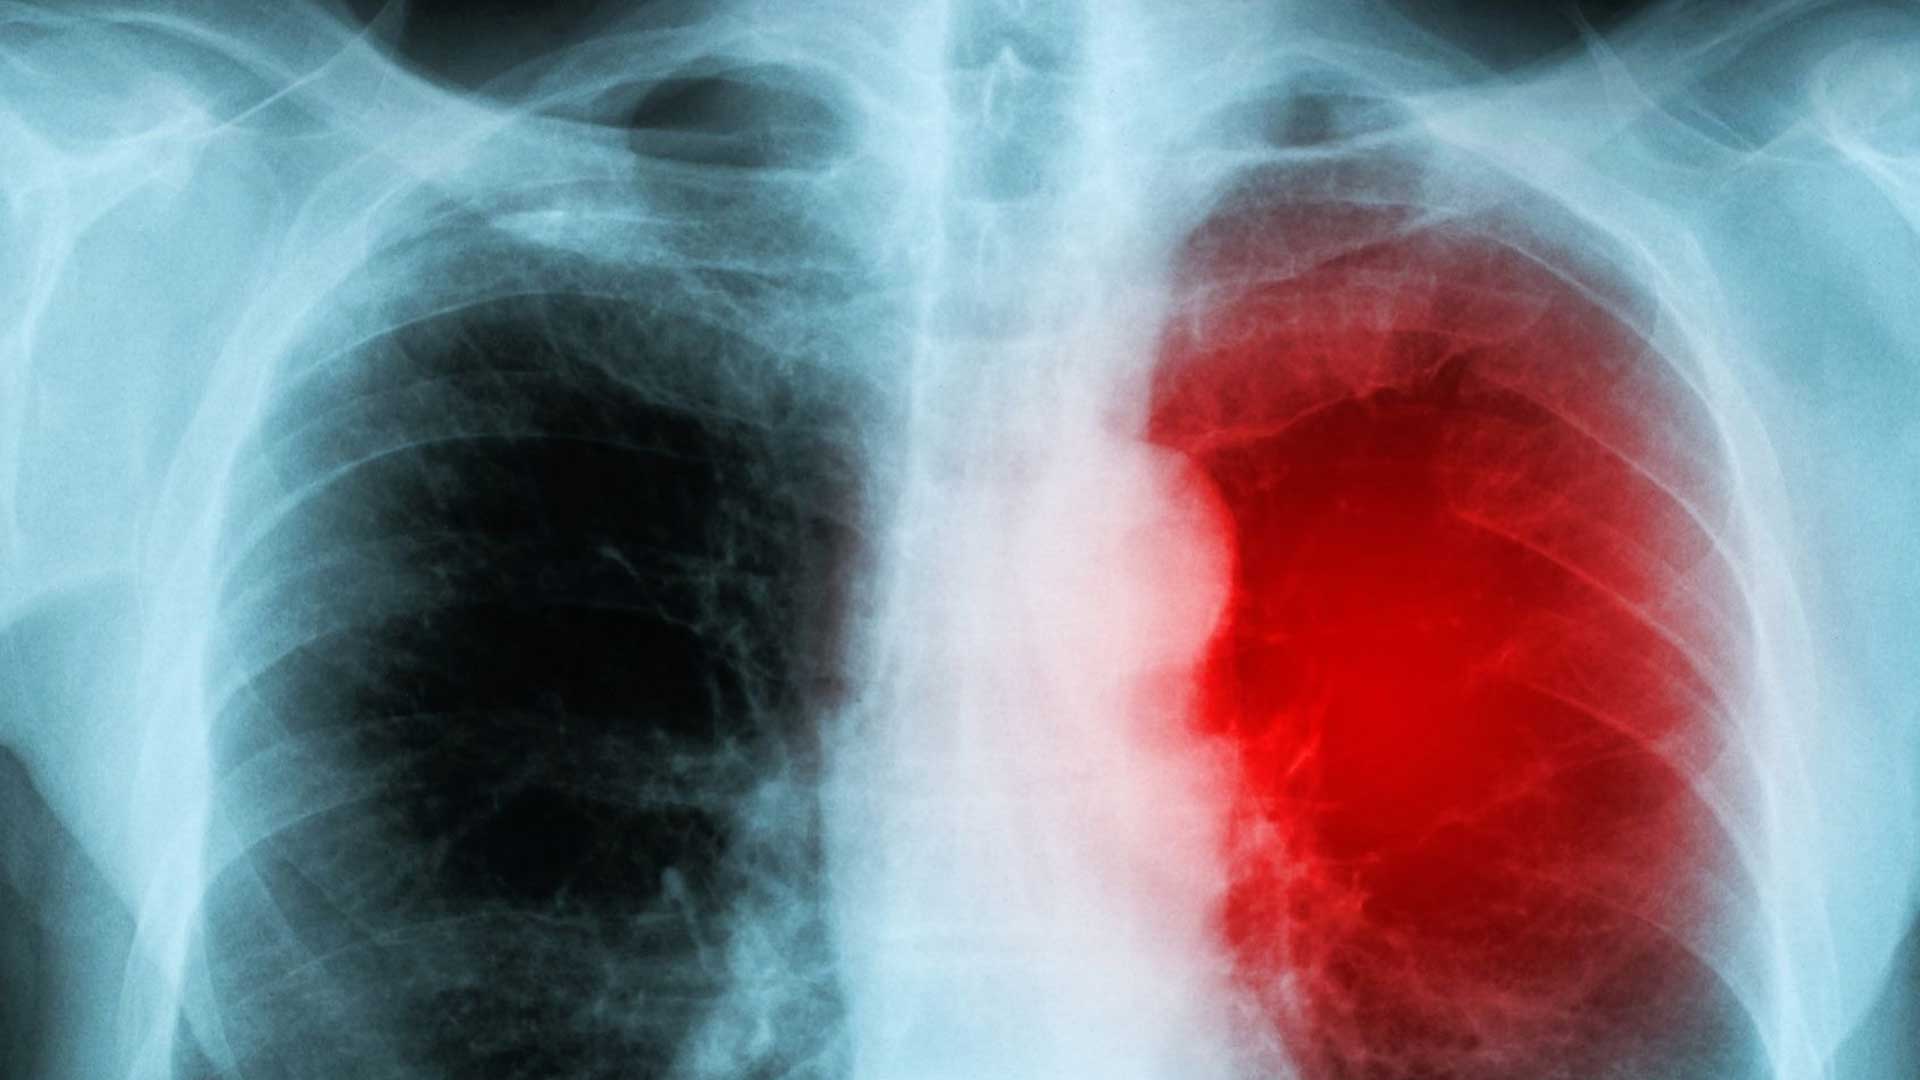

La miocarditis no es un efecto significativo de las vacunas, pero sí de COVID-19

La frecuencia de los casos de miocarditis tras recibir una vacuna es, por decir lo más: mínima. Se trata de un efecto adverso bien vigilado con poquísimos casos que responden bien al tratamiento, situación que dista mucho del riesgo de miocarditis como consecuencia de una infección como COVID-19, el cual es mayor e incluye afecciones diversas.

El COVID-19 sí aumenta el riesgo de miocarditis y su peligrosidad

El académico mexicano Mauricio Rodríguez señaló que para identificar riesgos de un tratamiento se debe comparar la vacuna contra la afección que se desea evitar. Esta es una evaluación que realizaron los Centros para el Control y la Prevención de Enfermedades de EU encontrando que el riesgo de miocarditis después de la infección con COVID-19 es mucho mayor, ya que “los pacientes con COVID-19 entre marzo de 2020 y enero de 2021 tenían, en promedio, 15.7 veces más riesgo de miocarditis en comparación con los que no tenían COVID-19”.

Uno de sus hallazgos fue que había “entre 1 y 10 eventos adicionales de miocarditis en 1 millón de personas vacunadas con una primera o segunda dosis, pero 40 casos adicionales en 1 millón de personas infectadas con COVID-19”.

Además, señalan “mayores riesgos de pericarditis y arritmias cardíacas después de una prueba positiva de SARS-CoV-2”, asociaciones que no se observaron luego de las vacunas. Este estudio también enfatiza que “el riesgo de morbilidad y mortalidad de por vida después de la infección por SARS-CoV-2 es sustancial”.